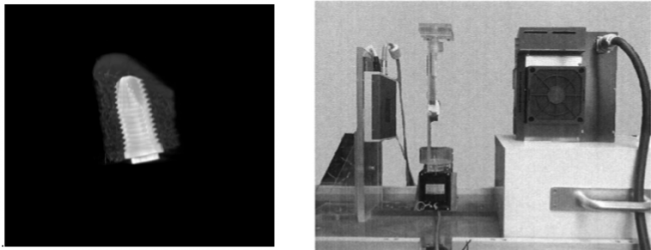

Scattered photons highly degrade the quality of X-ray images and their effect has become more important due to the increasing interest in cone-beam geometry for the acquisition of CT (CBCT) and micro-CT data. The random nature of scatter events and the great influence of the sample suggest that the most accurate methods for their estimation are Monte Carlo (MC) techniques, but their use is usually hampered by the large computation time required to obtain an acceptable estimation of the scattered radiation. We present an approach for scatter correction in CBCT by MC estimation, speeding up the computation by means of general purpose graphic processing units (GPGPU) and developing a framework for the automatic correction and reconstruction of projection data.

La calidad de imagen obtenida por equipos micro-TAC (tomografía axial computarizada) para pequeño animal depende en gran medida de la bondad del calibrado de los mismos. En la literatura previa se han propuesto diferentes métodos para el calibrado de cada uno de los parámetros de un sistema micro-TAC. Sin embargo, existen pocas referencias sobre el esquema de calibración global a seguir para obtener los mejores resultados. En este trabajo se presenta una propuesta para el calibrado global de equipos micro-TAC, que ordena los pasos del proceso y elimina posibles interdependencias entre los mismos.

This work presents an approach to extend the dynamic range of X-ray flat-panel detectors for cone-beam micro-CT by using two different acquisitions of the same sample, taken at two different X-ray photon fluxes with the same X-ray beam peak energy and filtration. Photon flux for the first scan is chosen as the maximum possible value not saturating the detector in the low attenuation areas. The second exposure level is calculated from the data acquired in the first exposure, assuming that the detector response to the incoming radiation is linear. |

El objetivo de este trabajo es la comparación de dos detectores de rayos X tipo “flat-panel” (C7940DK-02, C9321SK-05, Hamamatsu Photonics), para su uso en TAC de haz cónico de alta velocidad para pequeños animales. |